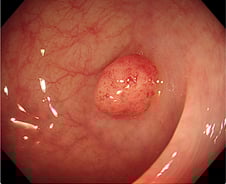

사람의 감정과 행동을 조종하는 기생충이 있다는 사실, 알고 계신가요? 기생충도 사람처럼 중추신경계가 있어 판단력을 갖추고 있는데요. 그중에서도 똑똑한 기생충으로 꼽히는 '톡소포자충'은 사람의 몸속에서 살다가 마지막 단계로 고양이 몸속으로 이동해 교배하는데, 이를 위해 숙주(사람)가 고양이를 좋아하게 만들어 고양이를 키우게 유도한다는 것으로 알려졌습니다. 해외 다수 연구에 따르면 톡소포자충에 감염된 쥐는 고양이 소변 냄새에 대한 공포감이 줄어드는 것으로 확인됐습니다. 또 톡소포자충에 감염된 남성이 그렇지 않은 남성보다 고양이 소변 냄새를 더 좋아했다는 연구 결과도 있습니다. 반면 여성 감염자는 비감염자와 별다른 차이가 없었습니다. '기생충이 몸 안에 들어오면 음식물을 대신 먹어 살이 빠질 것'이란 속설이 있습니다. 지난해 체중 감량에 어려움을 겪던 미국의 20대 여성이 기생충 알이 든 캡슐을 먹고 다이어트하려다 뇌·목·얼굴·혀·간·척추 등에 기생충이 퍼져 끔찍한 부작용에 시달렸다는 사연이 전해졌습니다.